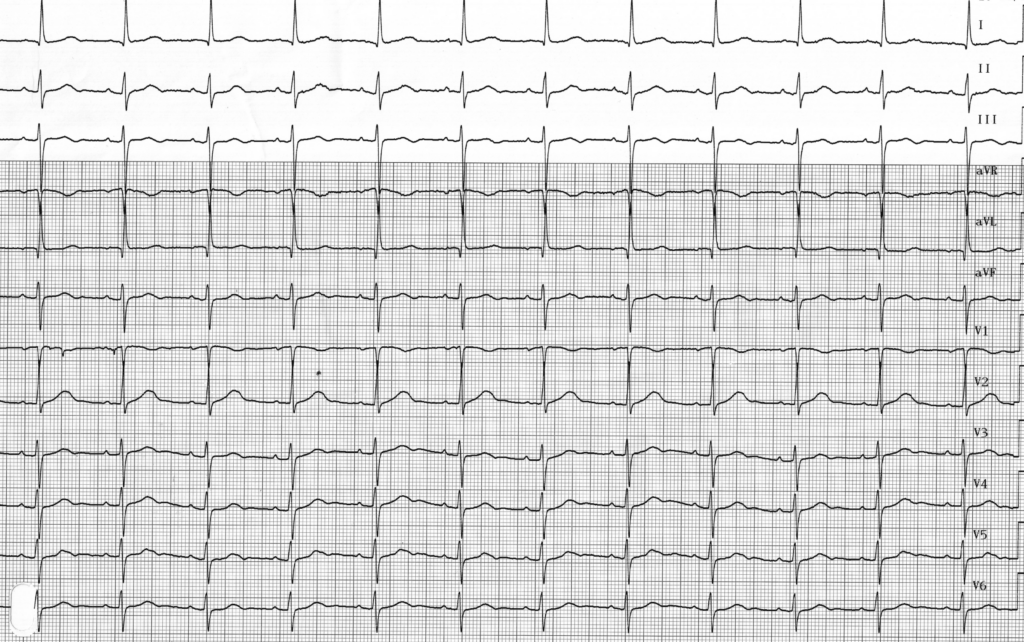

Sur ce premier tracé, le stimulateur a été programmé en mode 0D0. La spécificité de ce mode de “stimulation” est que la détection dans les 2 cavités est effective mais qu’aucune stimulation (atriale ou ventriculaire) n’est possible. Il est donc évidemment à proscrire chez les patients dépendants. Ce mode de stimulation permet donc une analyse du rythme spontané du patient avec visualisation concomitante de l’électrocardiogramme et des marqueurs d’évènements. Il s’agit d’un mode de test de sensibilité. Le mode 0D0 peut être programmé de façon temporaire chez les patients non dépendants porteurs d’un pacemaker IRM-compatible devant bénéficier d’une IRM. Le mode 0D0 de ces stimulateurs IRM compatible permet d’éviter l‘éventuelle réversion d’un mode 0D0 traditionnel vers un mode VVI. Il ne faut évidemment pas oublier de contrôler et reprogrammer le stimulateur après l’examen (en fonction des constructeurs).

Dans les tracés suivants, différents marqueurs sont utilisés:

AS (atrial sensing): détection atriale; VS: (ventricular sensing): détection ventriculaire; AP (atrial pacing): stimulation atriale; VP (ventricular pacing): stimulation ventriculaire;